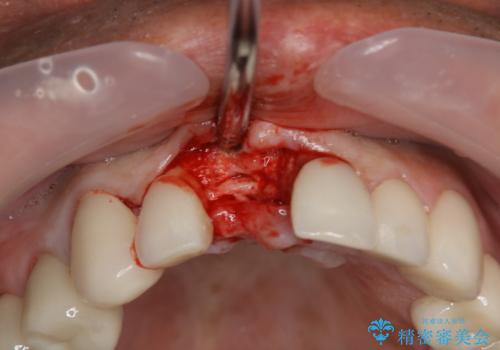

患者様のご要望もあり、審美性の確保ができる抜歯早期埋入→埋入後即時荷重という手術法を取りました。

近年、インプラントの素材や手術法の研究が進み、保存不可能となった歯牙に対して抜歯してすぐインプラントを埋入し、さらに直後から仮歯がを入れ噛むことができる【抜歯即時埋入】【即時荷重】という技法が確立されました。

- 外科手術のため、術後に痛みや腫れ、違和感を伴います